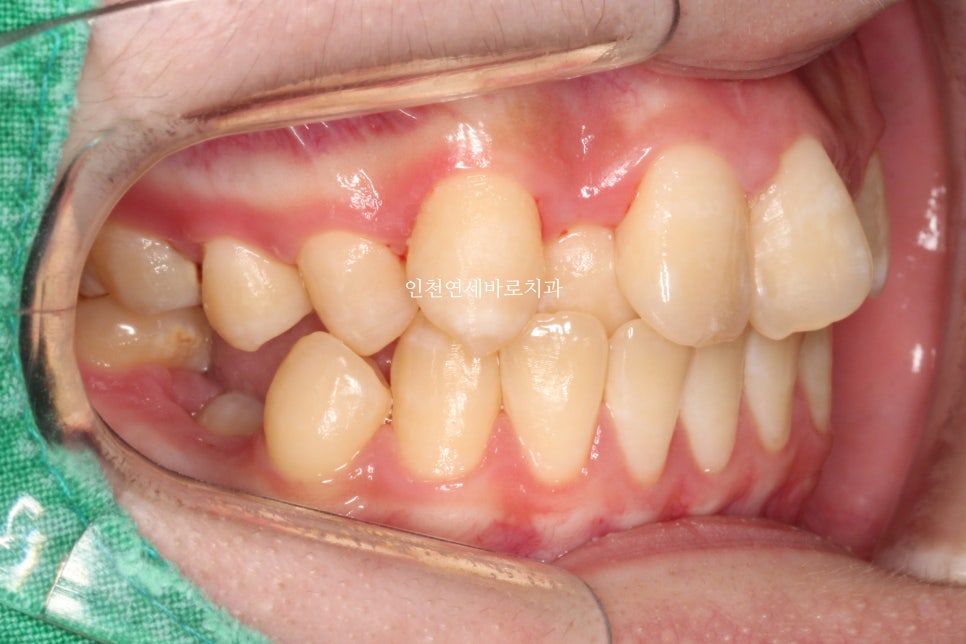

위와 같이 삐뚤삐뚤했던 치열을 가진 아이가 와서 #철사교정 치료를 하고

마무리가 되었습니다.

이 아이는 치료를 위해 #악궁확장 장치도 4개월간 사용하였습니다.

악궁확장장치의 사용까지 필요했던 아이로, 전체 치료기간이 조금 긴 느낌입니다.

2022.4.26. ~ 2024.5.27.

약 2년1개월이 소요되었네요